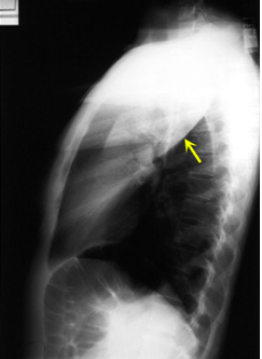

What is this consolidation?

LUL Consolidation